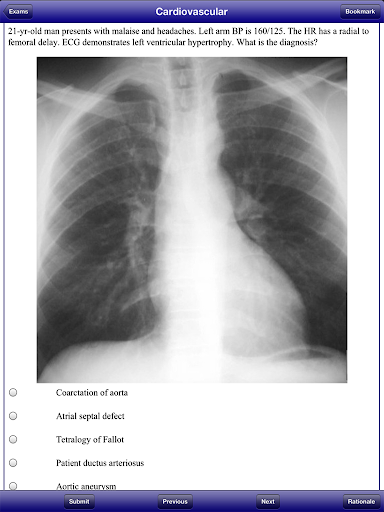

USMLE 2 Stanford Review Course, by David Nobel, MD, replicates the actual USMLE Step 2 Clinical Knowledge examination. USMLE 2 Stanford Review Course includes 1800 questions and answers written by trusted medical school professors who have reviewed the most recent USMLE 2 examination. USMLE 2 Stanford Review Course also includes 300 image format questions, including CT scans, MRIs, ECGs, and dermatology pictures.